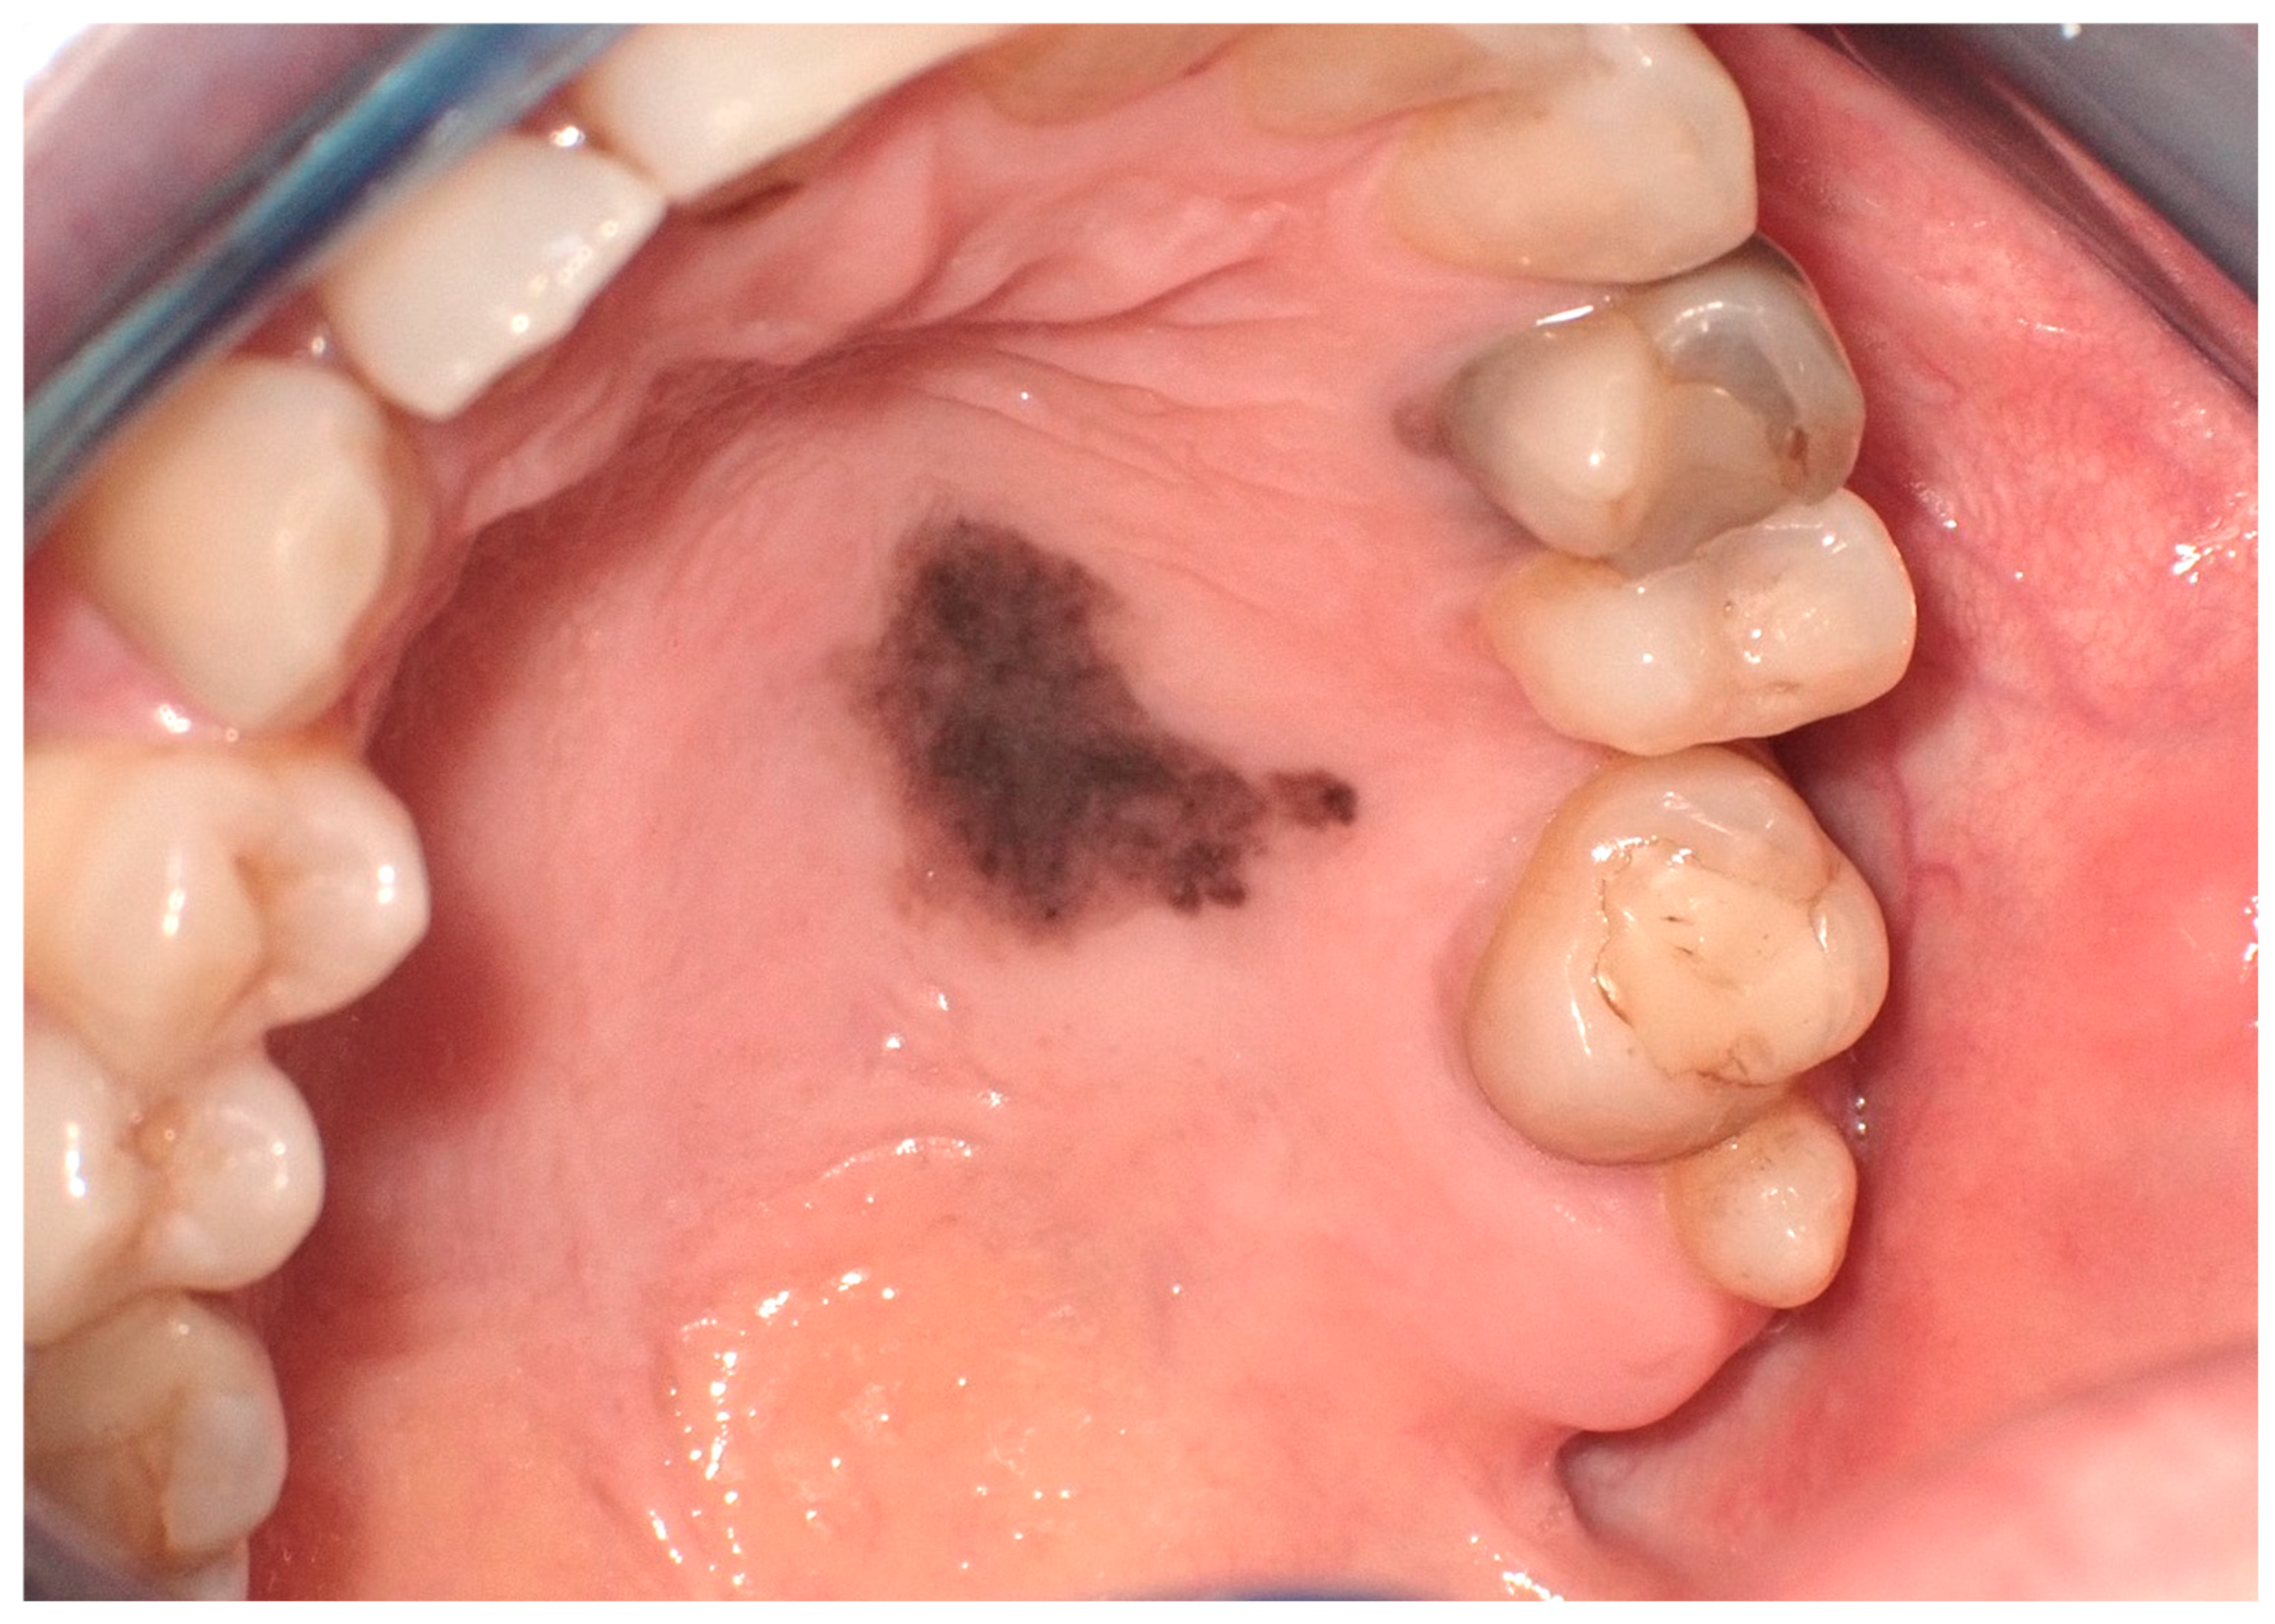

Clinically, these macules are commonly situated on the lower lip. However, their presence is not restricted to this region alone; presentations on the buccal mucosa, gingiva, hard and soft palates, and the dorsal surface of the tongue have been documented (Figure 3). These macules, typically isolated in appearance, vary in size, often occupying a few millimeters in diameter. Despite their benign character, the identification of oral melanotic macules warrants a comprehensive clinical assessment [9].

Figure 3.

Oral melanotic macula on the upper gingival mucosa on a 40-year-old patient. Patient refers to these lesions as being present since over 6 months. (archive S.A., patient signed the consent for clinical pictures).

The clinical evaluation of oral melanotic macules typically relies on comprehensive visual inspection and an in-depth review of the patient’s medical history. However, atypical features or documented changes in the lesion’s appearance necessitate additional diagnostic measures [10]. In this case, histological assessment through biopsy becomes essential. Histopathological findings often reveal increased melanin deposition in the epithelial basal layer and may include melanin-laden macrophages within the connective tissue, without a corresponding rise in the number of melanocytes [9].